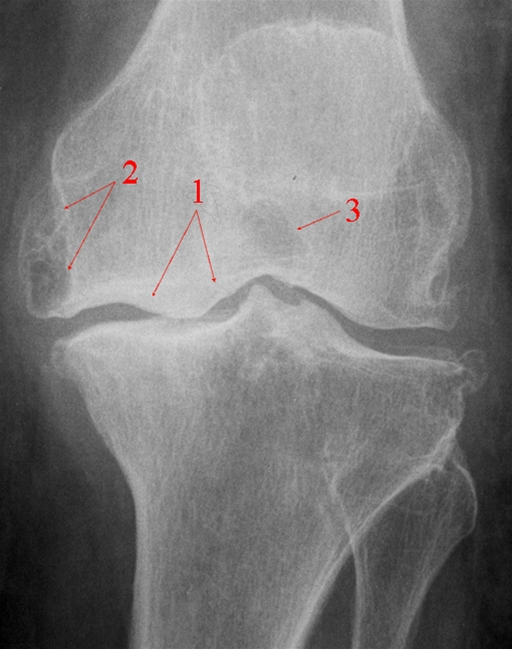

Frontalbillede af knæled med reduceret bruskhøjde, subkondral sklerosering (1), betydelige randudbygning (osteofyt) (2) og cystiske opklaringer (3).